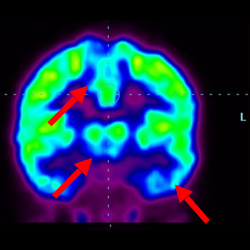

細胞治療后,藍色和黑色區域減少,并且看到更活躍的區域。這表明損傷減少并改善了大腦功能。

這證明細胞療法是治療腦癱兒童安全有效的方法。細胞療法可以更新大腦損傷的核心,并且可以通過 PET CT 掃描來監測大腦的改善情況。這些細胞療法與標準治療一起促進腦癱兒童的生長和改善。